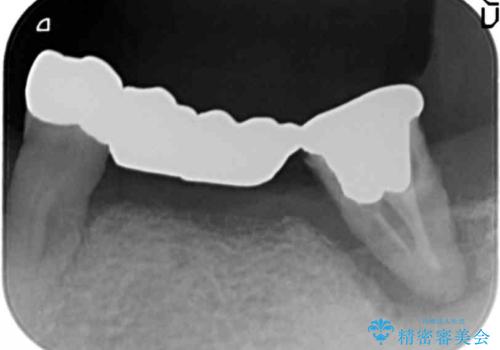

精査したところ、全顎的な重度の歯周病により左下のブリッジ(左下④56⑦)の著しい動揺を認めました。

禁煙指導と歯周病治療後、左下臼歯部(左下467埋入)のインプラント治療を行いました。

インプラントの埋入は、抜歯後4ヶ月程度骨の治癒を待ったり、骨が少ない部分に関しては骨増生を行ったりして順次行いました。

インプラントの種類:スプラインツイスト(HAコーティング)

固定様式:スクリュー固定

クラウンの種類:ベレッツァクラウン